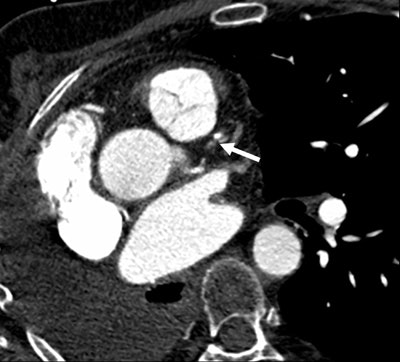

| Images 1-7 shown top to bottom: A 59-year-old man presented with atypical chest pain. A circumscribed, short-segment high-degree stenosis (arrow) in the proximal LAD is difficult to detect on transverse (1), sagittal (2), or coronal (3) multiplanar reformats. Use of advanced visualization tools with automated extraction of the coronary artery tree (4) and automated display as curved multiplanar reformat (5) clearly identifies the lesion, also seen in the 3D view (6) and confirmed on conventional catheter angiography (7). All images courtesy of Dr. U. Joseph Schoepf. |